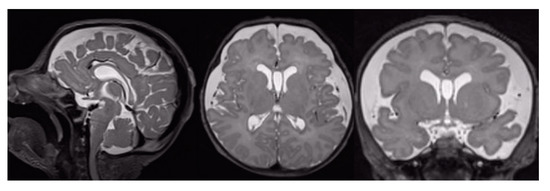

3.1. Conventional MRI Findings